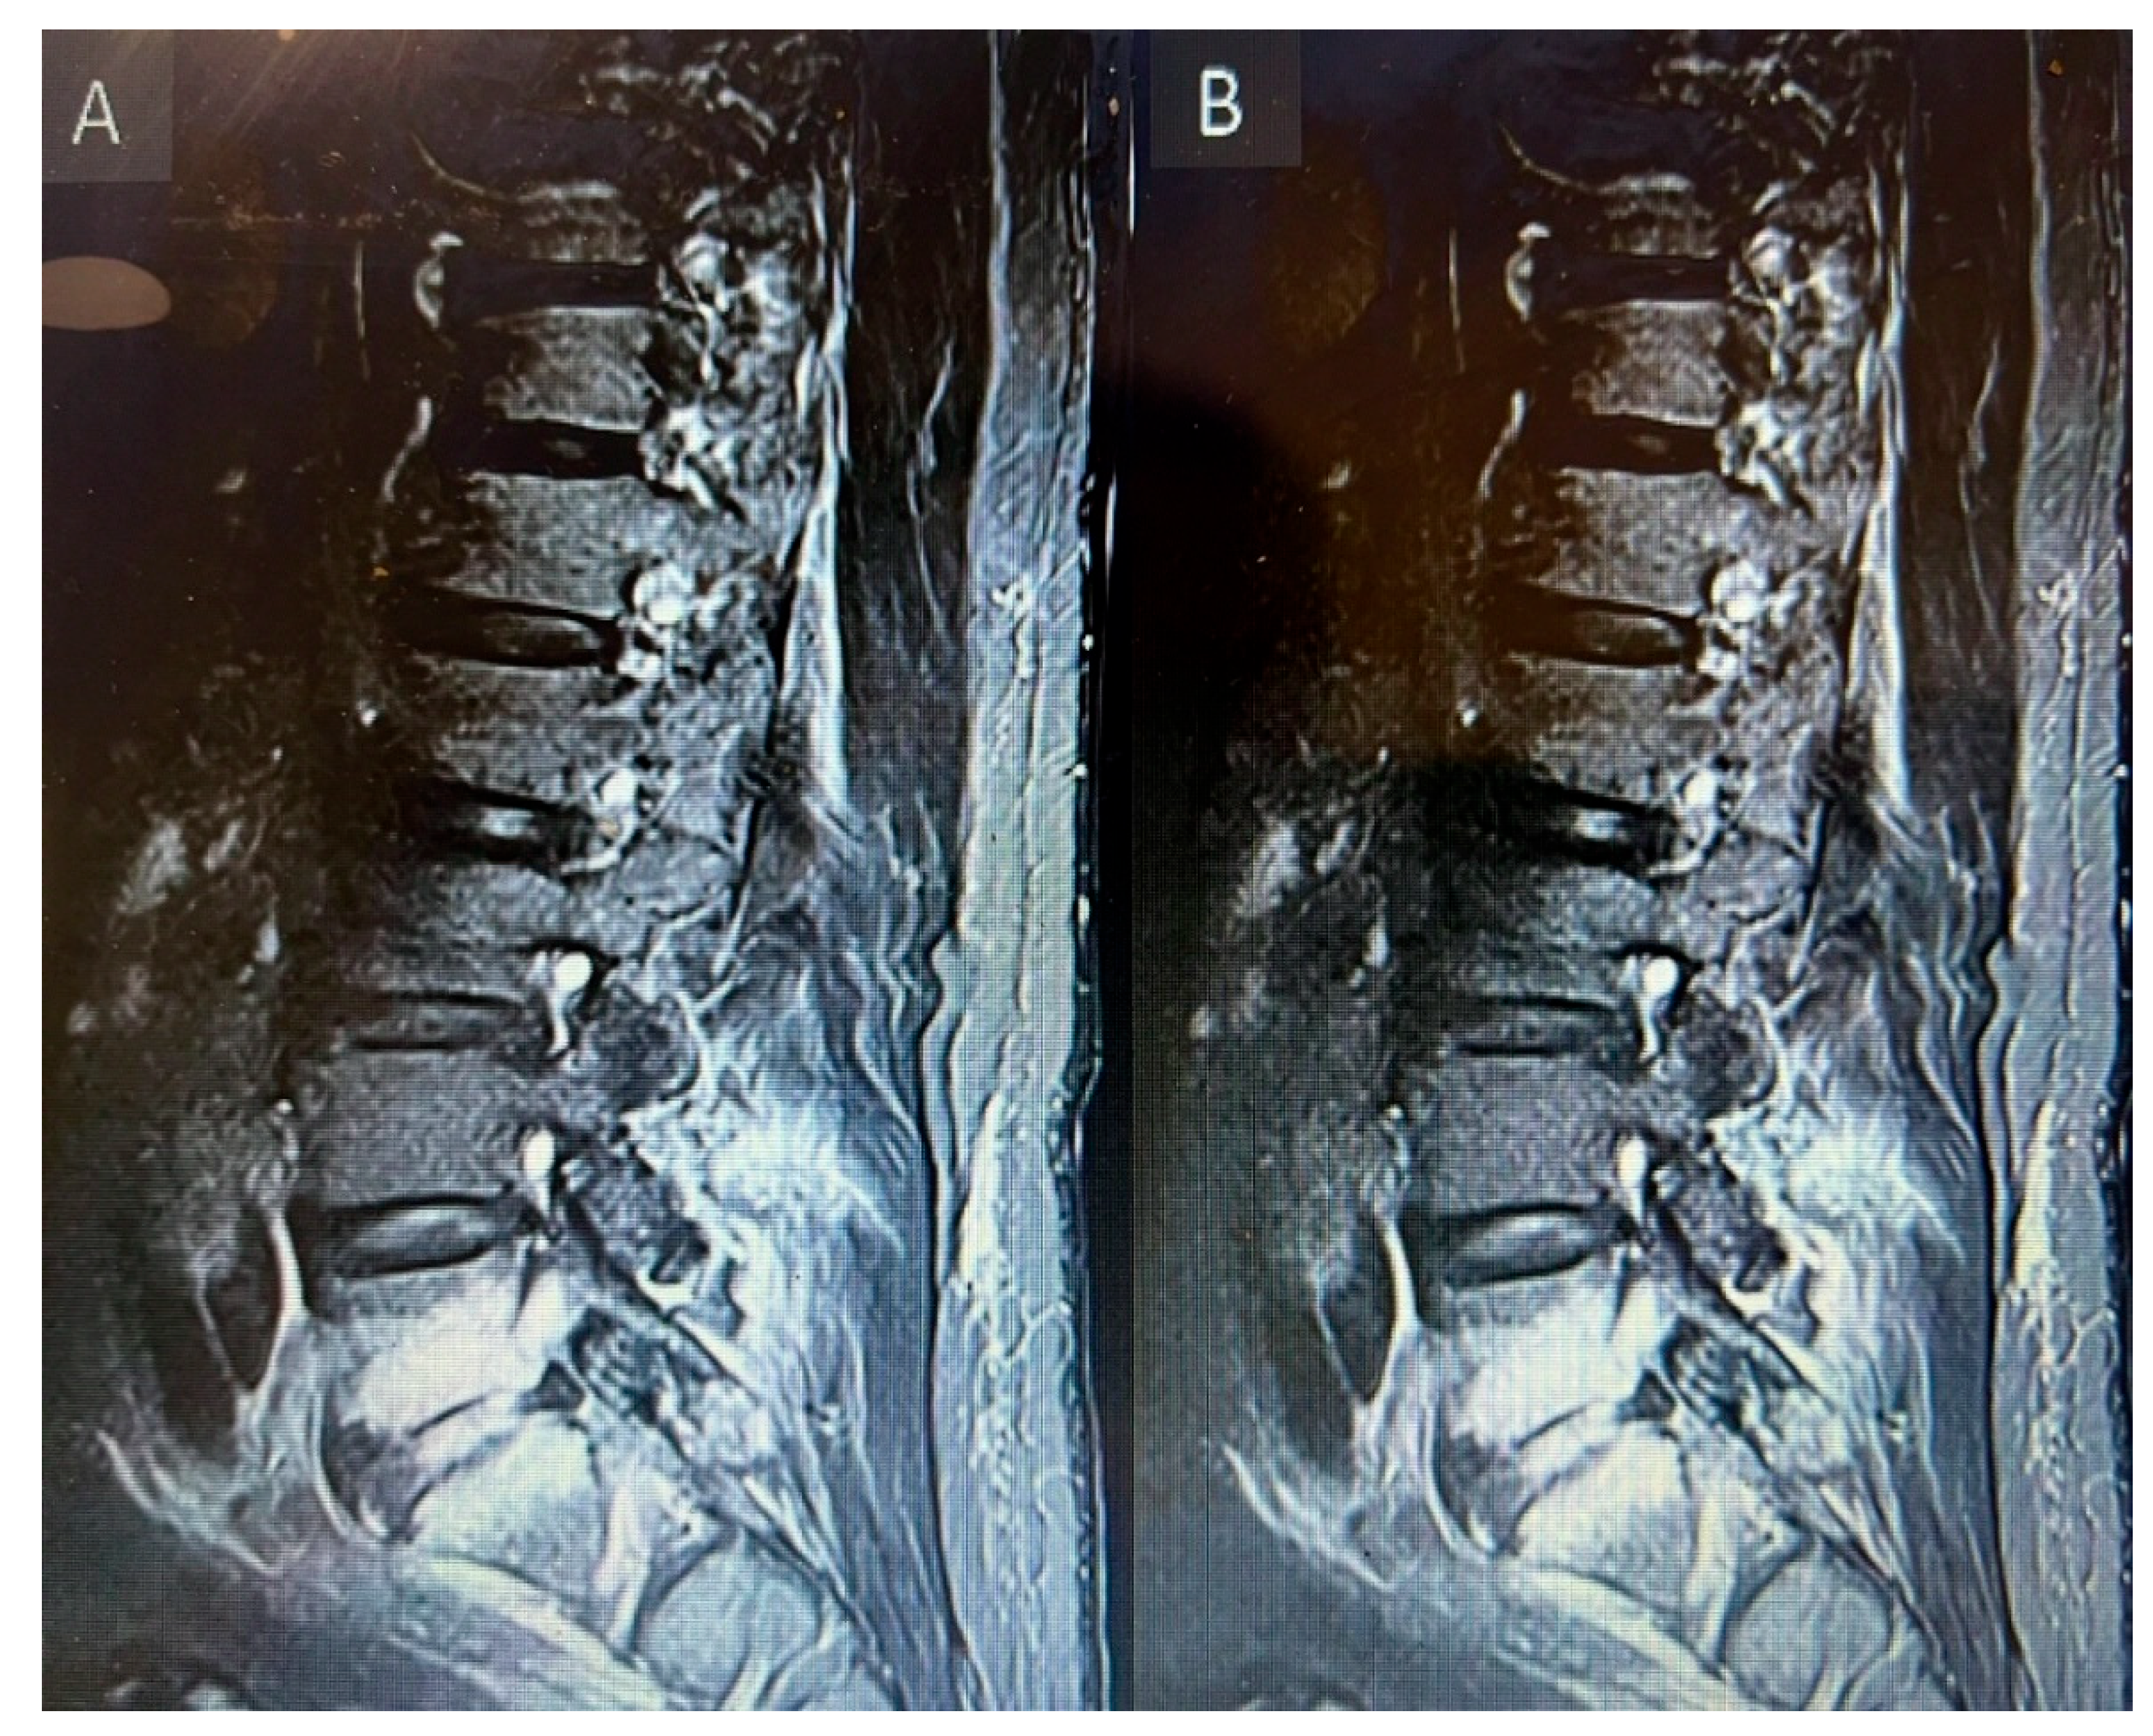

MRI Whole Spine: Severe central canal narrowing causing compression of the spinal cord with myelomalacia at C4/C5 level, with mild retrolisthesis at C4 over C5, thickening of the posterior longitudinal ligament, and ligamentum flavum hypertrophy. Various degrees of central canal narrowing and neural foraminal narrowing were noted at C3/C4, C4/C5, C5/C6, and C6/C7 levels, with additional findings including a small synovial cyst at C6/C7.

Figure 2. Preoperative MRI cervical spine T2 weighted sagittal (A) and axial (B) showing cord compression posteriorly with cord signal change at cervical 4 level.

Figure 6. MRI Lumbar spine short tau inversion recovery sequency sagittal views first MRI before starting anti gout medications (A) and follow up MRI after starting anti gout medications (B) showing spondylodiscitis at the level of lumbar 5, sacral 1 level.